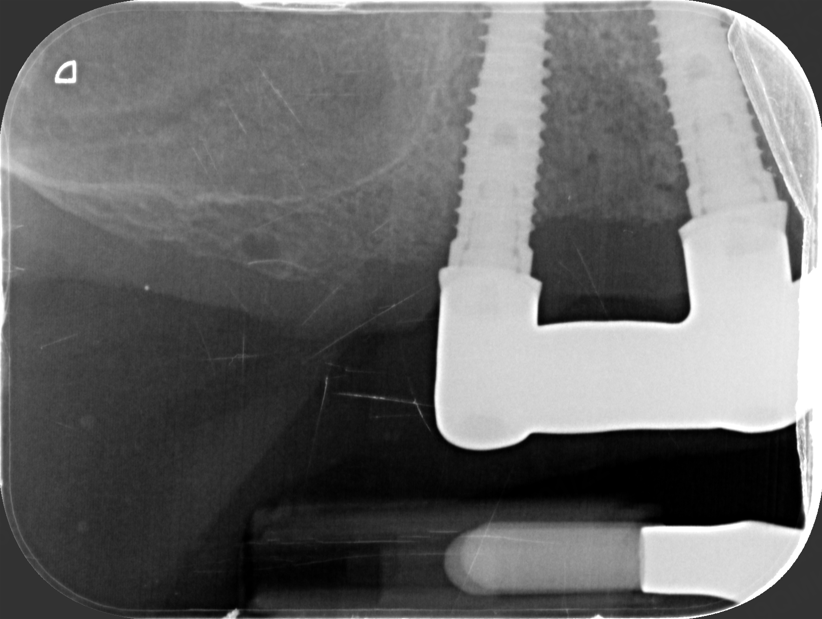

One week after surgery, when sutures were removed, the temporary prosthesis was also removed, and the metal bar was tested by performing the one-screw “Sheffield test”: the bar was screwed at one end, an intraoral x-ray was taken at the implant at the opposite end of the bar. The test was repeated switching sides. (Pics. 4-6).

Fig 5